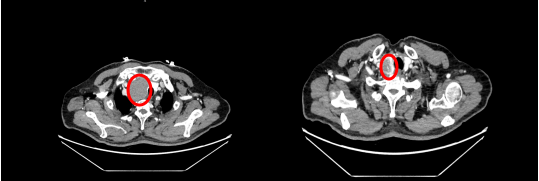

患者闫先生(化名)因无明显诱因出现声音嘶哑,吞咽困难,经检查发现其胸腔内存在一直径近7厘米的纵隔肿物,压迫喉返神经、食管,与心脏及肺组织比邻关系紧密。

由于患者高龄,且伴有高血压、慢性阻塞性肺疾病等基础疾病,手术面临三大挑战:一是肿物与心脏大血管及颈部血管、喉返神经紧密粘连,剥离时极易引发致命性出血及神经损伤;二是高龄患者对麻醉耐受性差,围术期风险陡增;三是术后肺部感染、呼吸衰竭等并发症概率高。多家医院曾因风险过高建议保守治疗,但患者及家属最终选择信任漯河市中心医院马广耀团队。

面对复杂病情,马广耀主任团队联合甲状腺外科、麻醉科、影像科等开展多学科会诊,定制个性化手术方案。采用胸骨正中切口入路,术中邀请甲状腺外科安兆峰主任共同主刀,在完整切除肿瘤的同时,巧妙避开主动脉、肺动脉、喉返神经等关键部位,将出血量控制在100毫升以内。麻醉团队运用精准液体管理,全程维持患者循环稳定。